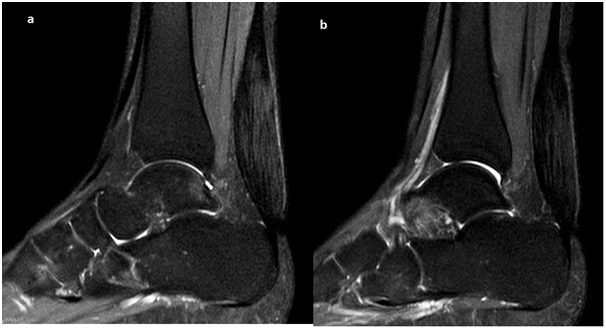

Laboratory tests revealed a normal complete blood count , inflamatuary markers and serological tests. Lipid profile revealed serum total cholesterol 269 mg/dl, serum triglyceride 97mg/dl , serum LDL cholesterol 144mg/dl and serum HDL cholesterol 106 mg/dl. Other blood parameters were within normal limits. Plain lateral radiographs of the ankles revealed bilateral soft tissue opacities in the region of the Achilles tendon without bone pathologies . In magnetic resonance imaging (MRI) of both ankles revealed bilateral enlarged Achilles tendons showing hypointensities on T1-weighted sequences and hyperintensities on T2-weighted and short T1 inversion-recovery (STIR) sequences. These findings were consistent with xanthoma (Figure 2). Cranial MRI revealed abnormal signal intensity characterized by hypointense T1-weighted and hyperintense T2-weighted echo images on supraventricular white matter of the left frontal and parietal lobe. MRI of sacroiliac joints were normal. ECG findings were within normal limits. It was thought that the diagnosis of the patient is CTX because on patient history, clinical and radiological findings. She was treated with ursodeodeoxycholic acid (750 mg/day). After 3 months of the treatment, cholesterol levels were back to normal, decreased swelling and completely healed the pain in Achilles tendon.

Figure 2 MRI of both ankles; revealed bilateral enlarged Achilles tendons showing hyperintensities on short T1 inversion-recovery (STIR) sequences.